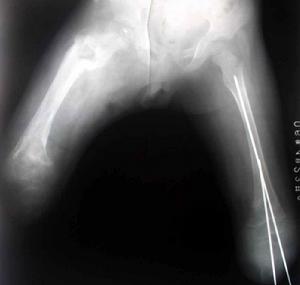

除了一般的理學檢查以外,有時因病情需要必須做一些檢驗,例如:驗血’照X-光若醫師懷疑骨髓炎的可能,會建議住院做進一步檢查與治療,有時因初始症狀輕微,而所有檢驗也在正常的範圍內,但醫師基於經驗及專業判斷,強烈懷疑骨髓炎時,也會給予注射抗生素,以免因不明顯的潛伏期(事實上細菌一直不停的繁殖,持續破壞骨骼,只是外表看不出來罷了)而空做等待,使病情更為惡化;因為等x-光出現骨骼破壞變化時往往已經太遲,很多家長不了解這種情形,往往會懷疑醫師的醫術,小則要求轉院,大則興師問罪,委實替有心之醫療人員澆了一盆冷水,甚至因此採取消極保守的治療方式,不但造成醫病關係的緊張,也易使病情更進一步惡化,實在得不償失!其實這也是嬰幼兒骨髓炎既特別又令人莫可奈何之處!